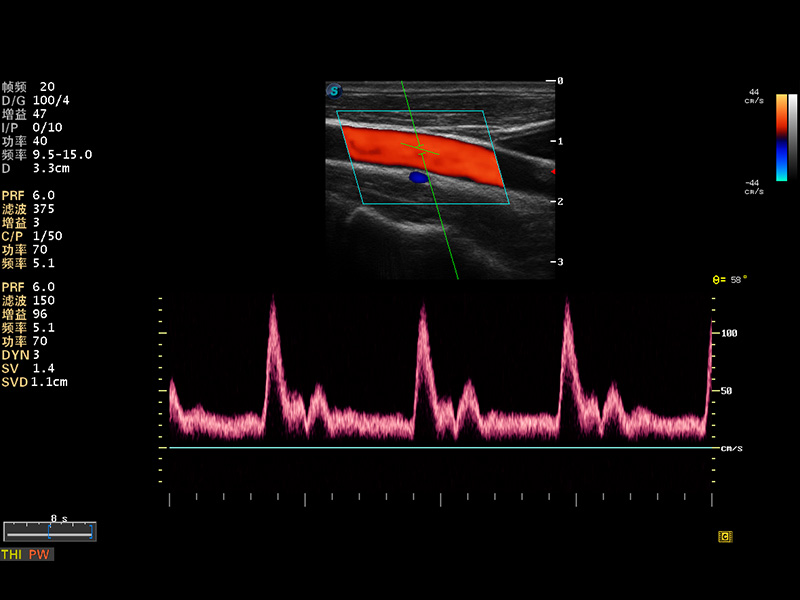

S8 EXP便攜式彩色多普勒超聲診斷儀是開立醫(yī)療研發(fā)的高端全身應(yīng)用型便攜彩超。高通道的VIS平臺融合可視化(Visual)、智能化(Intelligent)和人性化(Smart)的特點,配以開立醫(yī)療自主研發(fā)生產(chǎn)的探頭大家族,使您能夠快速、準確的獲得病人信息,提高工作效率的同時減輕疲勞。

成像技術(shù)

多波束形成器

μ-Scan微米成像

諧波成像

實時寬景成像

空間復(fù)合成像

3D/4D成像